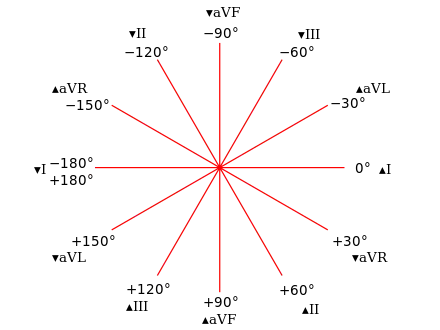

RV inflow view showing marked right ventricular hypertrophy Hexaxial reference system

Hexaxial reference system.jpg.webp) ECG showing right axis deviation

Electrocardiography

The use of electrocardiogram (ECG) to measure cardiac chamber hypertrophy is well established but since the left ventricular activity is dominant on the ECG a large degree of RVH is often required for any detectable changes. Nonetheless, the ECG is used to assist with the diagnosis of RVH. A post mortem study on 51 adult male patients concluded that anatomical RVH may be diagnosed using one or more of the following ECG criteria:[9]

- Right axis deviation of more than (or equal to) 110° (see hexaxial reference figure)

- R-wave dominant over S-wave in V1 or V2

- S-wave dominant over R-wave in V6

However, the American Heart Association recommended the use of additional diagnostic tests to diagnose RVH because no single criteria or set of criteria were considered sufficiently reliable.[10]